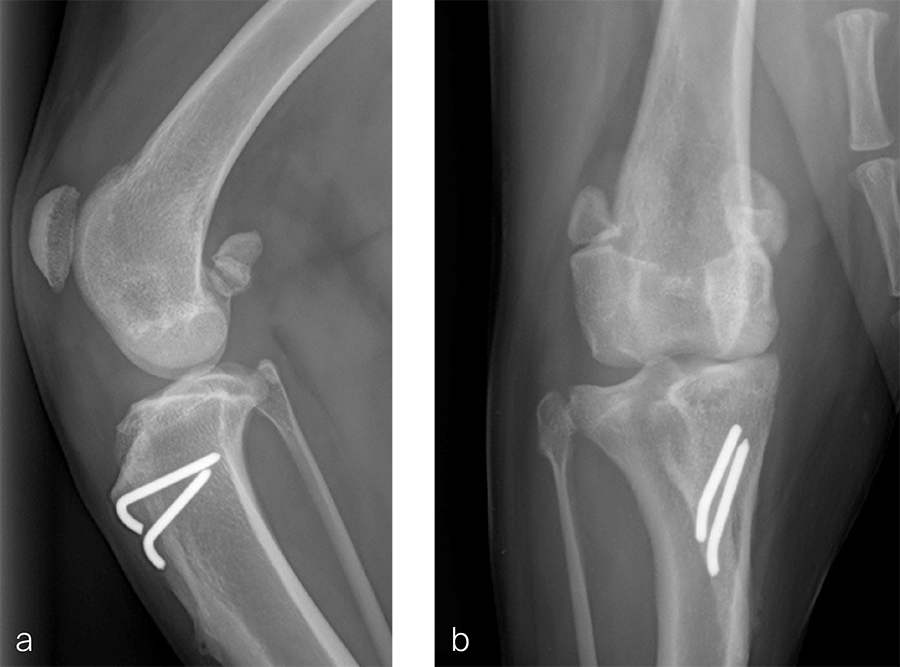

A 1.5 year old spayed female Appenzell Cattle Dog weighing 29 kg presented for a second opinion after two previous surgical procedures (Fig 7 and Fig 8) to address a traumatically induced medial patellar luxation. Orthopedic examination and preoperative radiographs revealed a grade 3/4 medial patellar luxation (Fig 8). Femoral varus was documented (aLDFA 104°; normal 92–96°) by CT scan (Fig 9 ). The planned correction was a 10° lateral closing wedge ostectomy, with concurrent sulcoplasty. Click here to read through the detailed surgical procedure.

Fig 7a–b Initial surgery performed at 1 year and 6 months of age. The patellar luxation was treated with a lateral imbrication. No primary orthopedic procedures were performed. Radiographs were obtained six weeks postoperatively, and document persistence of the medial patellar luxation.

Fig 8a–b Revision surgery performed to address persistent patellar luxation. A tibial tuberosity transposition was performed to realign the insertion of the patellar tendon without addressing femoral deformity. Radiographs were obtained two months postoperatively. The patellar luxation persists despite transposition of the tibial tuberosity.